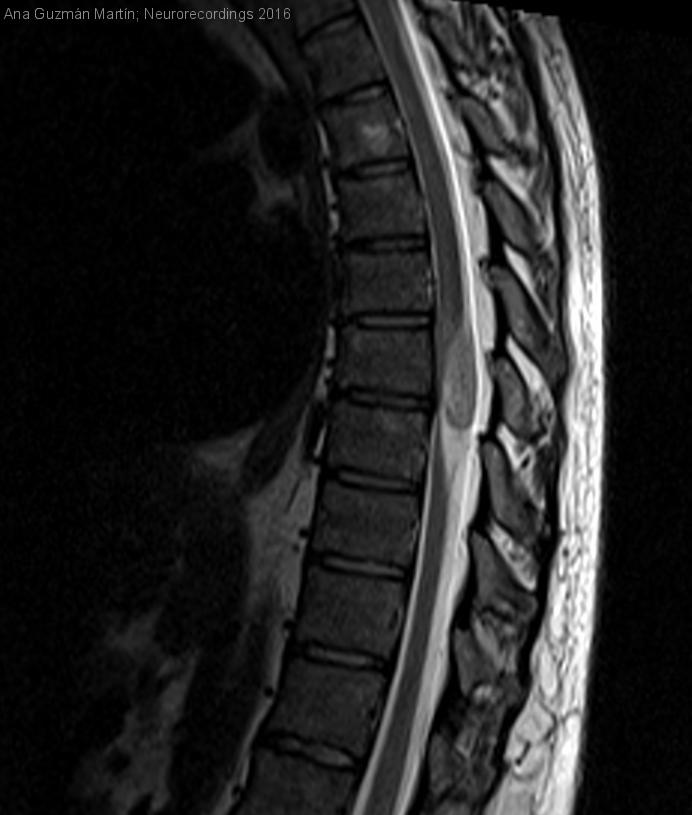

Hombre | 40 años

Diagnóstico final: Schwannoma dorsal

Presenta clínica desde los 28 años de sensación de descarga eléctrica o calambre en rodilla izquierda tanto en reposo como haciendo ejercicio físico, de unos segundos de duración.

Estos síntomas habían progresado a lo largo de los años hasta...